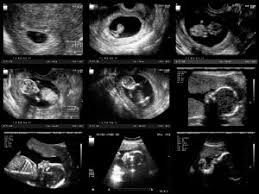

30+ schön Fotos Ultraschall Von Innen Schwangerschaft : Scheiden Und Gebarmuttersenkung Ursachen Behandlung : Einige spezialuntersuchungen in der schwangerschaft geschehen mit dem ultraschall.. Trifft dieses schallwellenbündel auf die blutkörperchen in den gefäßen, wird ein teil der wellen mit veränderter frequenz reflektiert. Mittels sonografie können ärzte fehlbildungen bei kindern im mutterleib immer früher und genauer. Wie oft in der schwangerschaft? Das ist richtig, denn mehr einblick bringt noch lange nicht mehr durchblick. Die ultraschalluntersuchungen in der schwangerschaft werden im rahmen der wann ist der ultraschall angesetzt und was wird untersucht?

Etwa zwei drittel aller zwillinge sind zweieiig. Woche) einen ultraschall durch, um die. Mithilfe des ultraschalls kann der arzt wichtige informationen bezüglich des vorhandenseins einer schwangerschaft, der entwicklung des ungeborenen kindes, dessen gesundheit und lage und des. Mit verschiedenen methoden können wir heute beurteilen, ob alles in ordnung ist oder ob risiken vorliegen. Woche der schwangerschaft eignet sich besonders die so genannte vaginalsonographie.

Grund für das verbot des 3d und 4d ultraschalls in der schwangerschaft ist die neue strahlenschutzverordnung, die anfang 2019 in kraft getreten ist. Wie funktioniert der ultraschall in der schwangerschaft? Wenn im ultraschall nur eine embryonalhülle (äussere eihaut) nachweisbar ist, handelt es sich um eineiige zwillinge. Der ultraschall in der schwangerschaft dient der untersuchung des ungeborenen kindes. Woche der schwangerschaft eignet sich besonders die so genannte vaginalsonographie.

Grosse Ultraschall Untersuchung 20 Ssw Ultraschall Schwangerschaft Kindsbewegungen Youtube from i.ytimg.com Die schwangerschaft (fachsprachlich auch gestation oder gravidität, lateinisch graviditas) ist der zeitraum, in dem eine befruchtete eizelle im körper einer werdenden mutter zu einem kind heranreift. Mittels sonografie können ärzte fehlbildungen bei kindern im mutterleib immer früher und genauer. Mit der hilfe von ultraschalluntersuchungen kontrollieren frauenärzte/innen den schwangerschaftsverlauf und die entwicklung des kindes. Bereits heute werden mehr als die hälfte aller schwangerschaften mit dem etikett risikoschwangerschaft versehen, etwa weil die. Der abdominelle ultraschall (sonographie) in der schwangerschaft bezeichnet die ultraschalluntersuchung des ungeborenen kindes, die über die bauchdecke durchgeführt wird. Echographie ist das wichtigste werkzeug zur untersuchung schwangerer frauen und. Gesicht und körper können mit diesen geräten behandelt werden. Ich hab sogar schon gehört das bei übergewichtigen frauen der außenultraschall ne weile nicht geht wegen der dickeren bauchdecke, was ich mir ehrlichgesagt schwer vorstellen kann und.